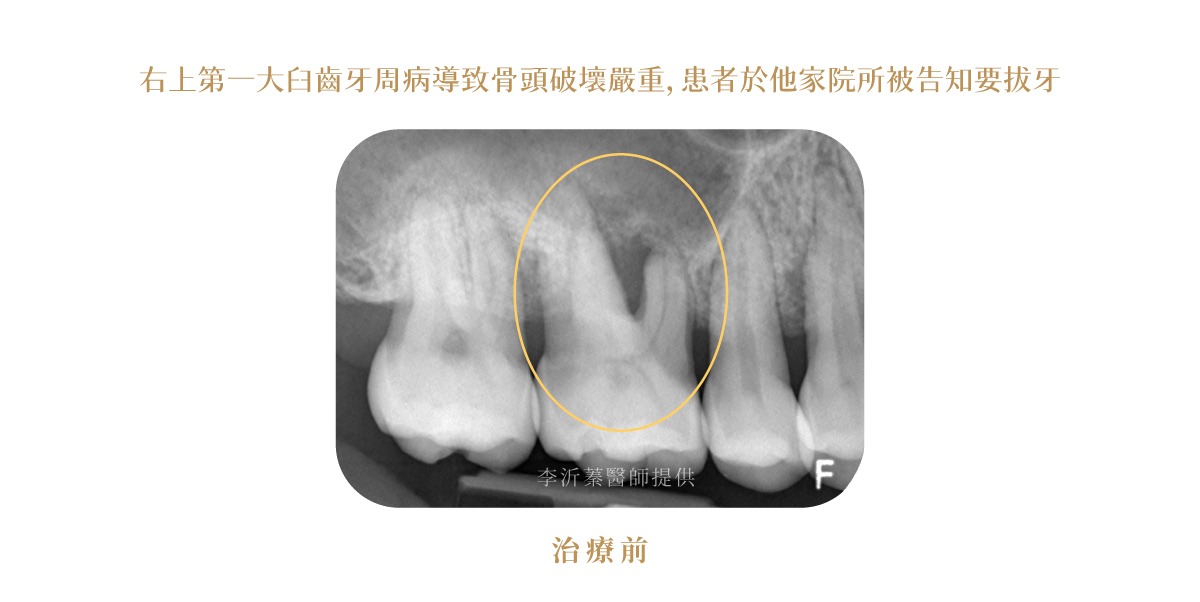

水雷射牙周治療案例